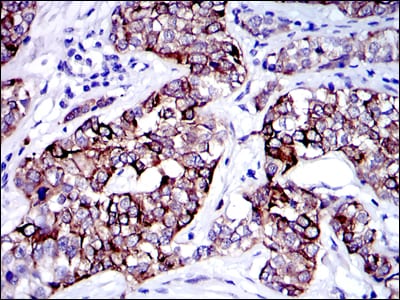

Immunohistochemical analysis of paraffin-embedded human cervical cancer tissues using KRT19 mouse mAb with DAB staining.

Immunohistochemical analysis of paraffin-embedded human colon cancer tissues using KRT19 mouse mAb with DAB staining.

Immunohistochemical analysis of paraffin-embedded human stomach cancer tissues using KRT19 mouse mAb with DAB staining.

Immunohistochemical analysis of paraffin-embedded human bladder cancer tissues using KRT19 mouse mAb with DAB staining.